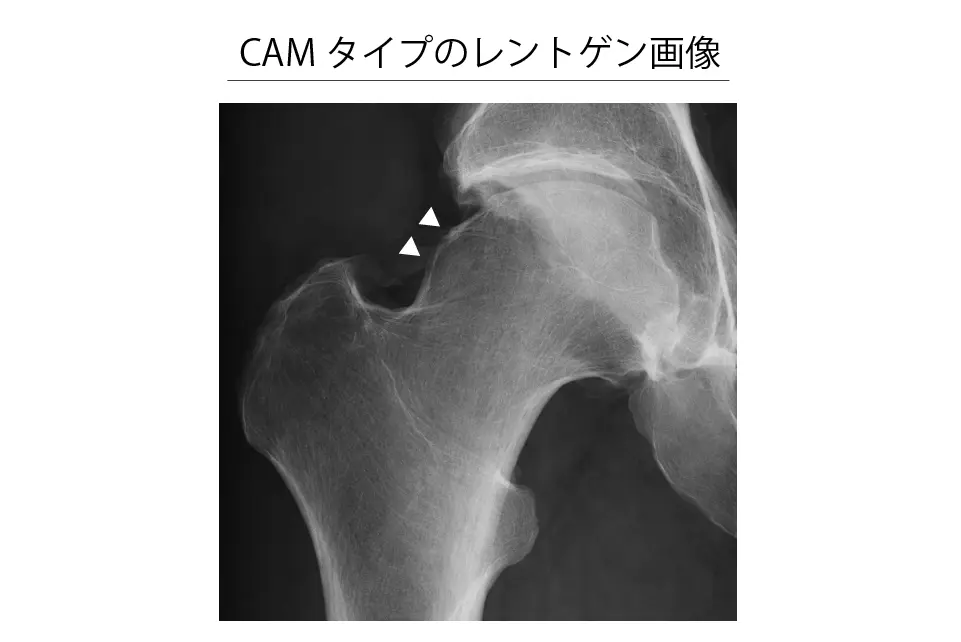

CAMタイプ

- CE角(中心‐縁角)が25°以上

- 主な所見:α角が55°以上

- 補助的な所見:

- head-neck offset ratioが0.14未満(骨の首部分のくびれが少ない)

- pistol grip変形(骨の形がピストルのグリップのように見える)

- herniation pit(骨の表面に小さなくぼみがある)